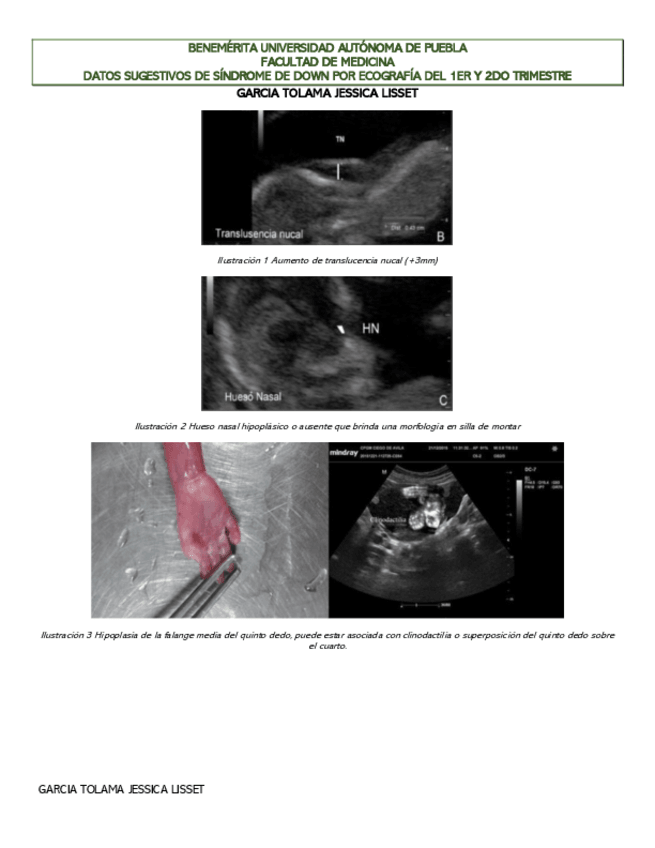

He publicado nuevos apuntes de 8º Obstetricia: SIGNOS-US-EN-EMBARAZO.pdf